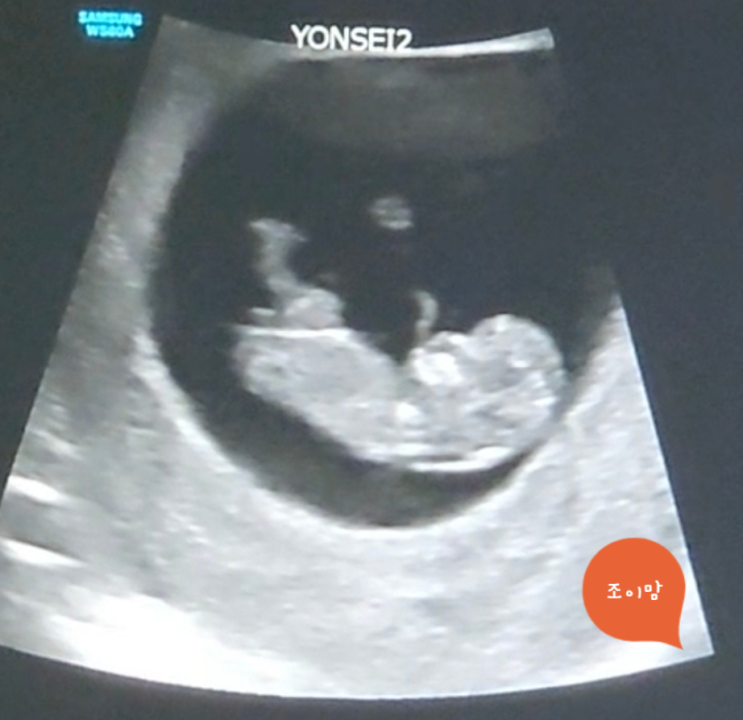

임신 12주, 기형아 검사(NIPT)를 받다.

안정기라고 불리는 임신 12주가 되었다. 12주가 되면 기형아 검사를 시행하는데, 나는 첫째 때와 동일하게 ...

임신 10주 차, 신촌 세브란스로 전원 성공!

오랜만에 들른 블로그. 근황 토크부터 시작해 보겠다. 현재 나는 둘째를 가진 임신부이며, 첫째 때 없었던 ...